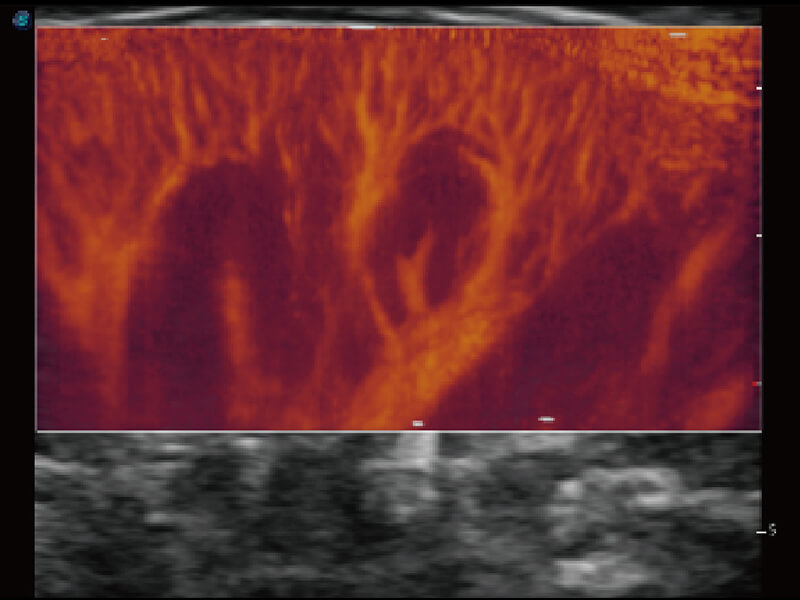

S60探头工艺,从前端信号处理每一个环节采集无损声学数据,真实还原组织原貌,再现解剖细节。

超宽频带技术,为容积成像带来优质的二维图像基础,为您呈现丰富的结构细节,栩栩如生地展示宝宝的宫内形态以及各种组织的立体结构。